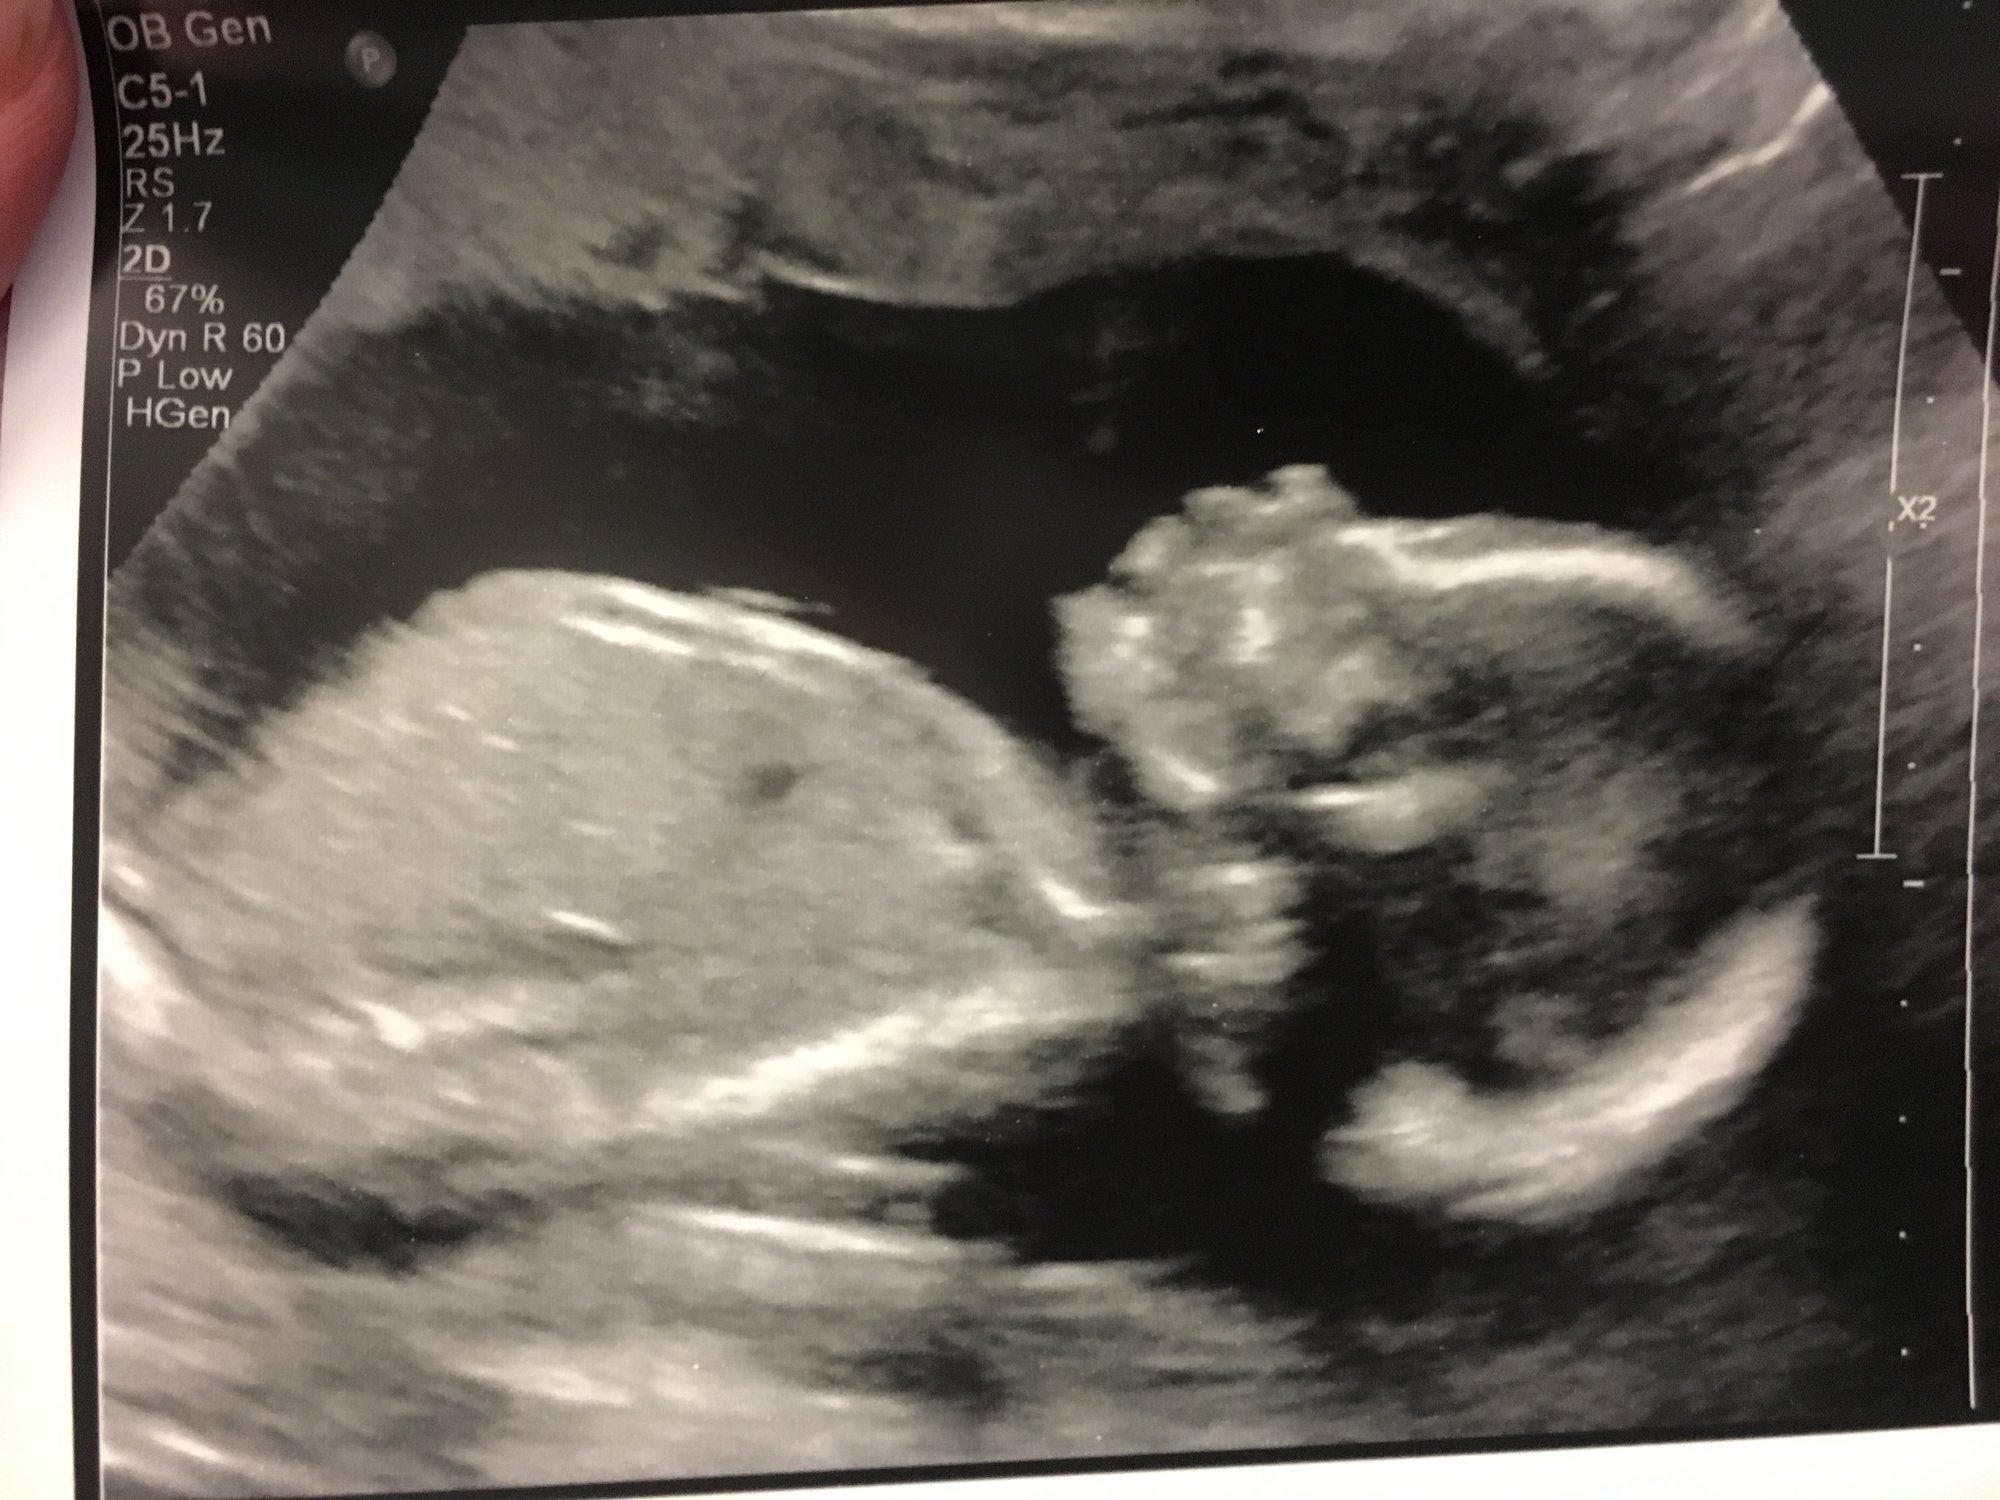

• @Hopeful_mom aww what a cutie!!! So glad it went well and you had a great tech :)

• @Hopeful_mom What an amazing picture! All of my anatomy scan pictures were not very clear. My baby just wasn't cooperating that day. I showed them to my parents and they were like ok. Didn't even know what we were looking for!

we also had our anatomy scan today too. He was swimming around everywhere and we confirmed it was a boy too. He wasn’t cooperating that much so I’m surprised she got a decent picture. Exciting for everyone getting theirs as we finally get to see the babies again after such a long break.

• @Hopeful_mom look at that little cutie pie! Love that. :)

• @holls214 awwww how cute - love it and I got a foot pic too soooo funny!  She showed me the baby pressing the foot down and i didn't feel it...so its interesting.  Did they tell you the size of the baby.  I believe mine is 13oz :)  I didn't get the inches next time ;)  @ReesaAnne16 and yes i think of all the IVF weight and i can't even let that get me down...from each cycle even from the IUIs i gained a couple of lbs and they all just added up...its worse now cause u just feel like a bigger marshmallow each day!!

@helloworld9 many of my pics were blurry I posted the best one, I"m thrilled!! We were spoiled with Vag US getting up close and personal with our beans as the belly sono looked like the babe shrunk at first.  At first my baby thought they were a lil cat all curled up and then luckily they started stretching :)

• such great u/s pics @Hopeful_mom@Holls214 :) and so glad everything came back clear!  I am having my anatomy scan on Monday and am starting to get nervous for it.  I hope I can just relax and enjoy it.

• Great pics @Holls214 !